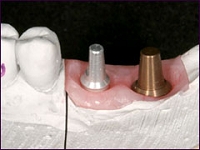

インプラントとは

インプラント治療とは、失ってしまった自分の歯の替わりに、人工の歯根を顎の骨に埋め込み、その上に人工の歯を作製して噛み合わせを回復する治療法です。

固定性であるためガタついたりせず、白分の歯のように噛めるようになります。

インプラント

人が物を噛むときの力は、想像以上に大きいものです。でも、丈夫なインプラント(人工歯根)なら、天然歯の歯根と同様に機能します。また歯冠の色や形も、最新の歯科技術によって、自分の歯と同じように作ることが可能です。